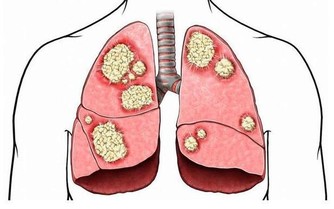

- 各種病菌在這樣的環境中容易滋生、繁殖,人們易通過呼吸道而感染此病。

- 膝蓋、頸椎等關節部位特別容易受冷風侵襲,引起頸椎病、肩周炎、風濕、類風濕等。

- 空調房低溫、乾燥又缺氧,會使人體免疫力有所下降,病菌特別容易乘虛而入。

空調清潔不到位或者不及時,散熱片中的細菌超標可達1000倍以上。

這些細菌隨呼吸道進入人體,容易導致人體出現頭暈乏力,甚至患上感冒、鼻炎、哮喘等上呼吸道疾病;重則引起下呼吸道疾病如肺炎,嚴重的還會因為呼吸衰竭而死亡。